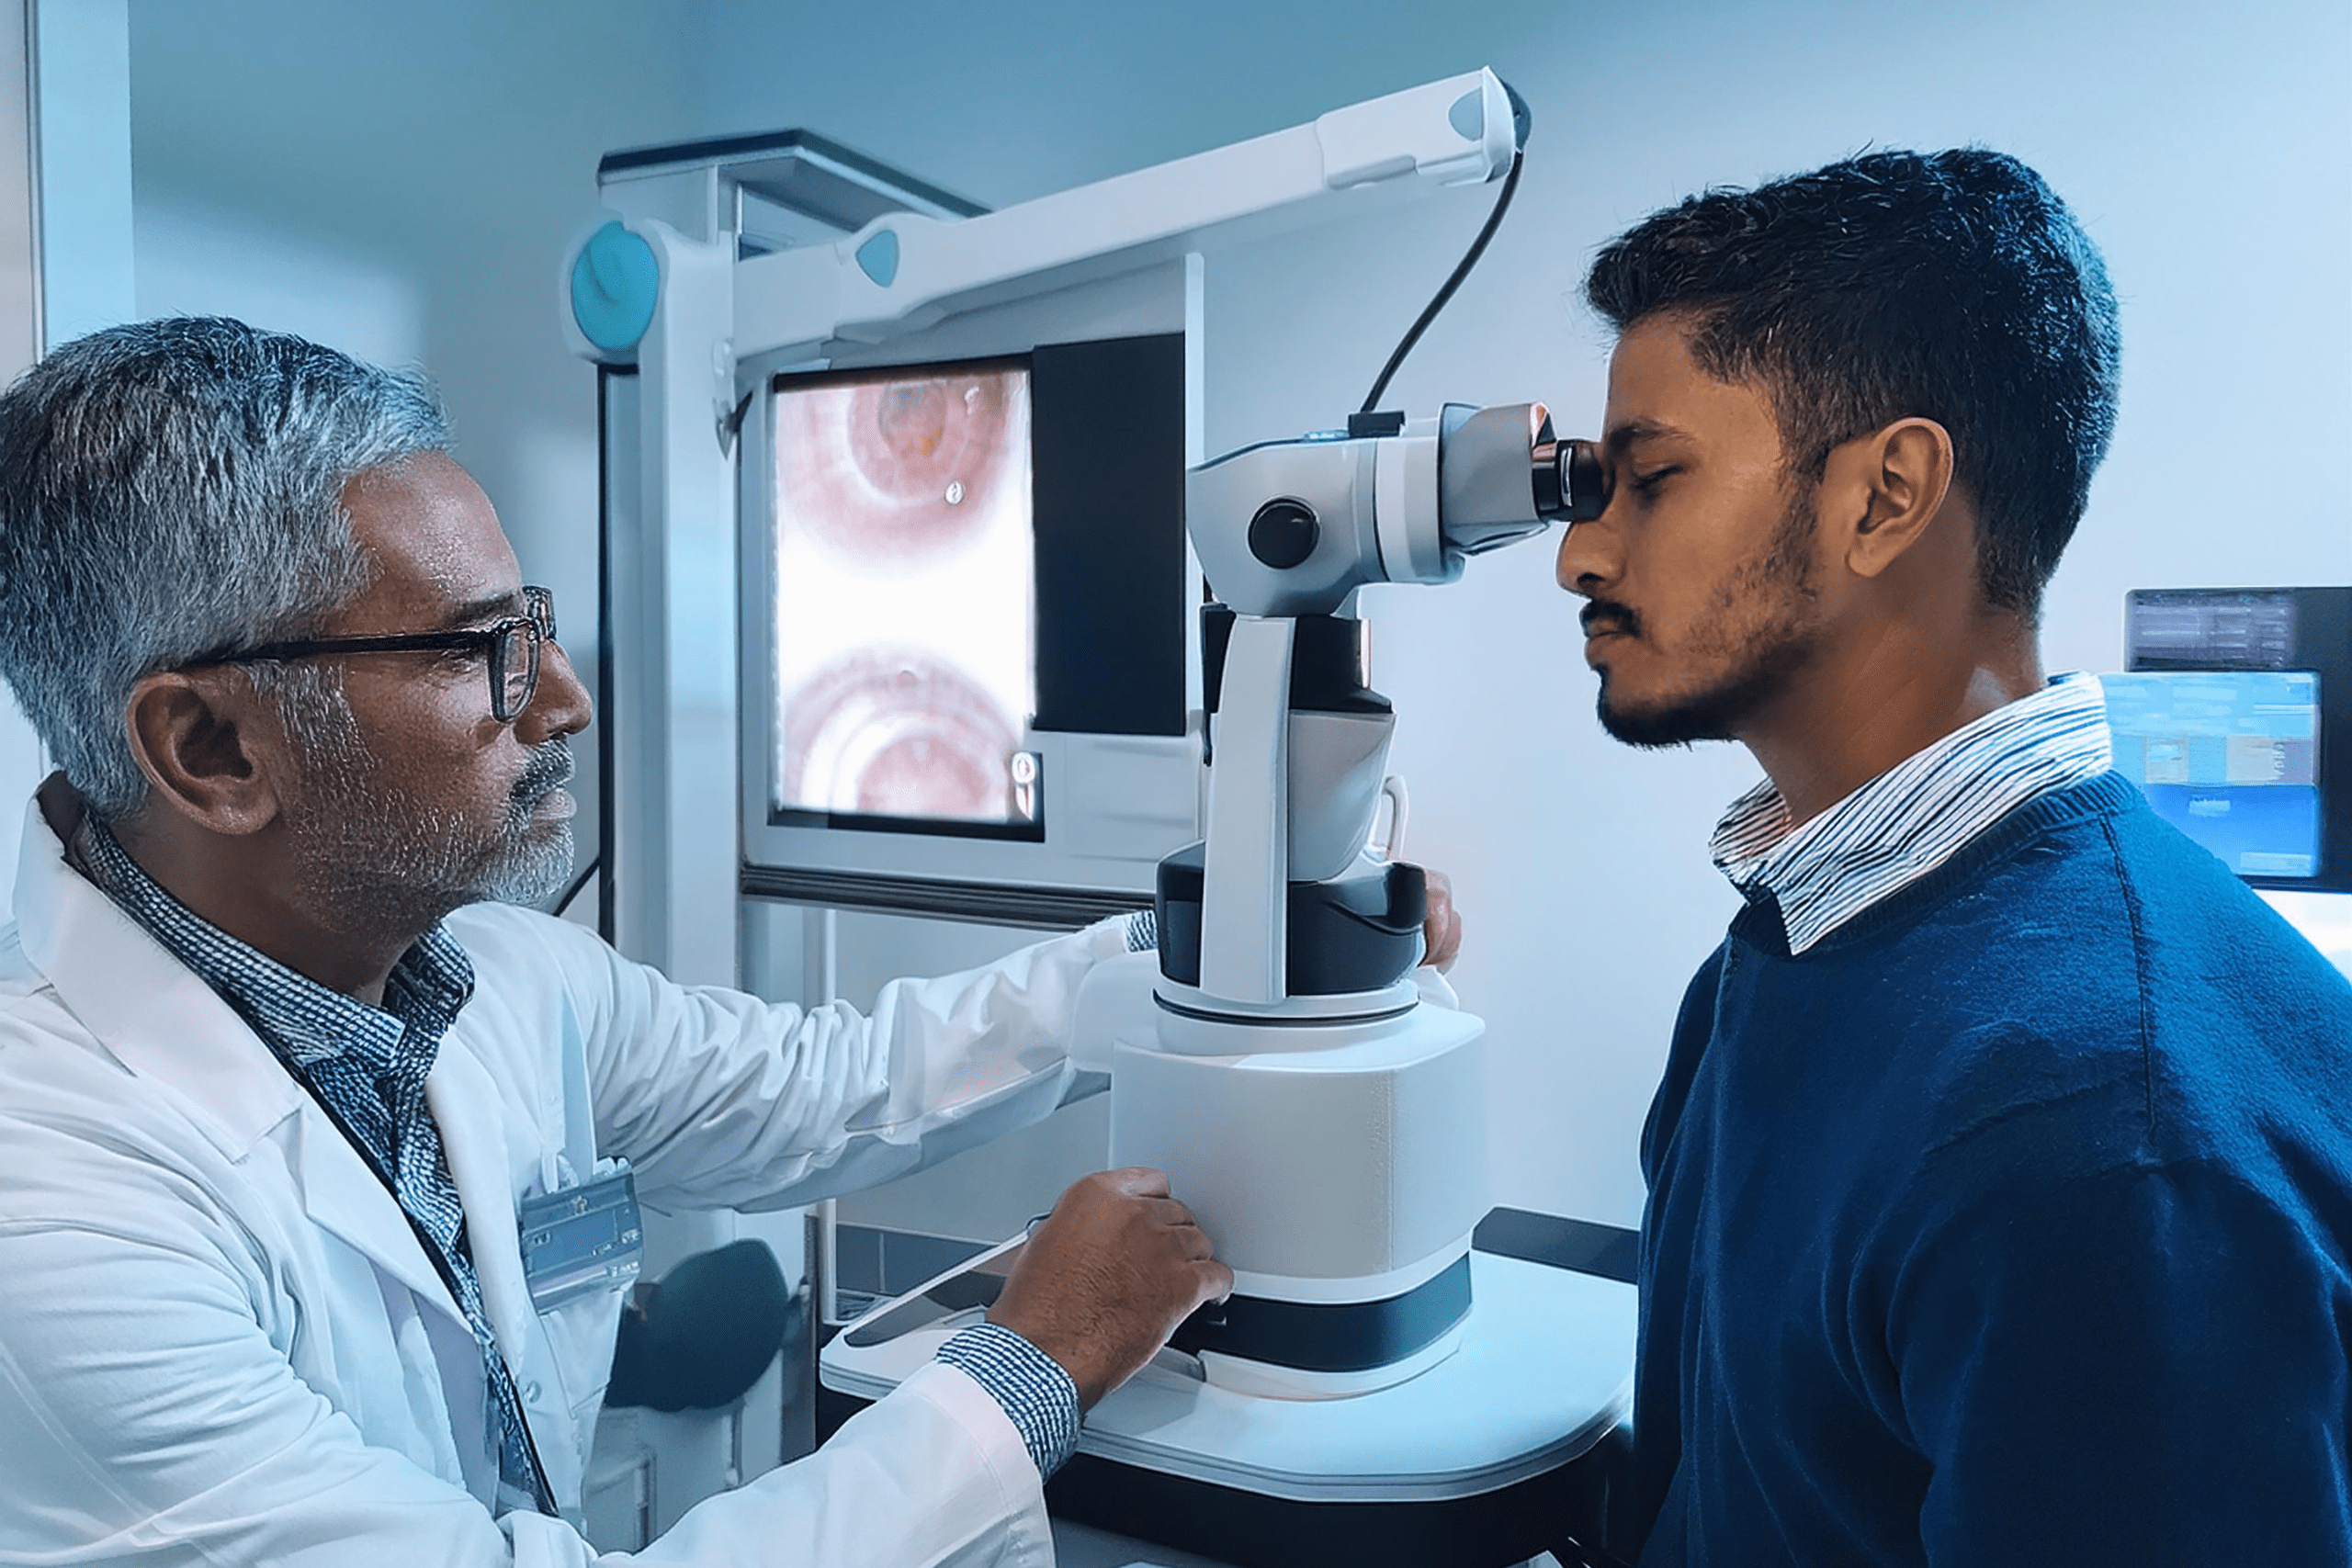

Best ICL Surgeon in Ambikapur

At Amrita Hospital